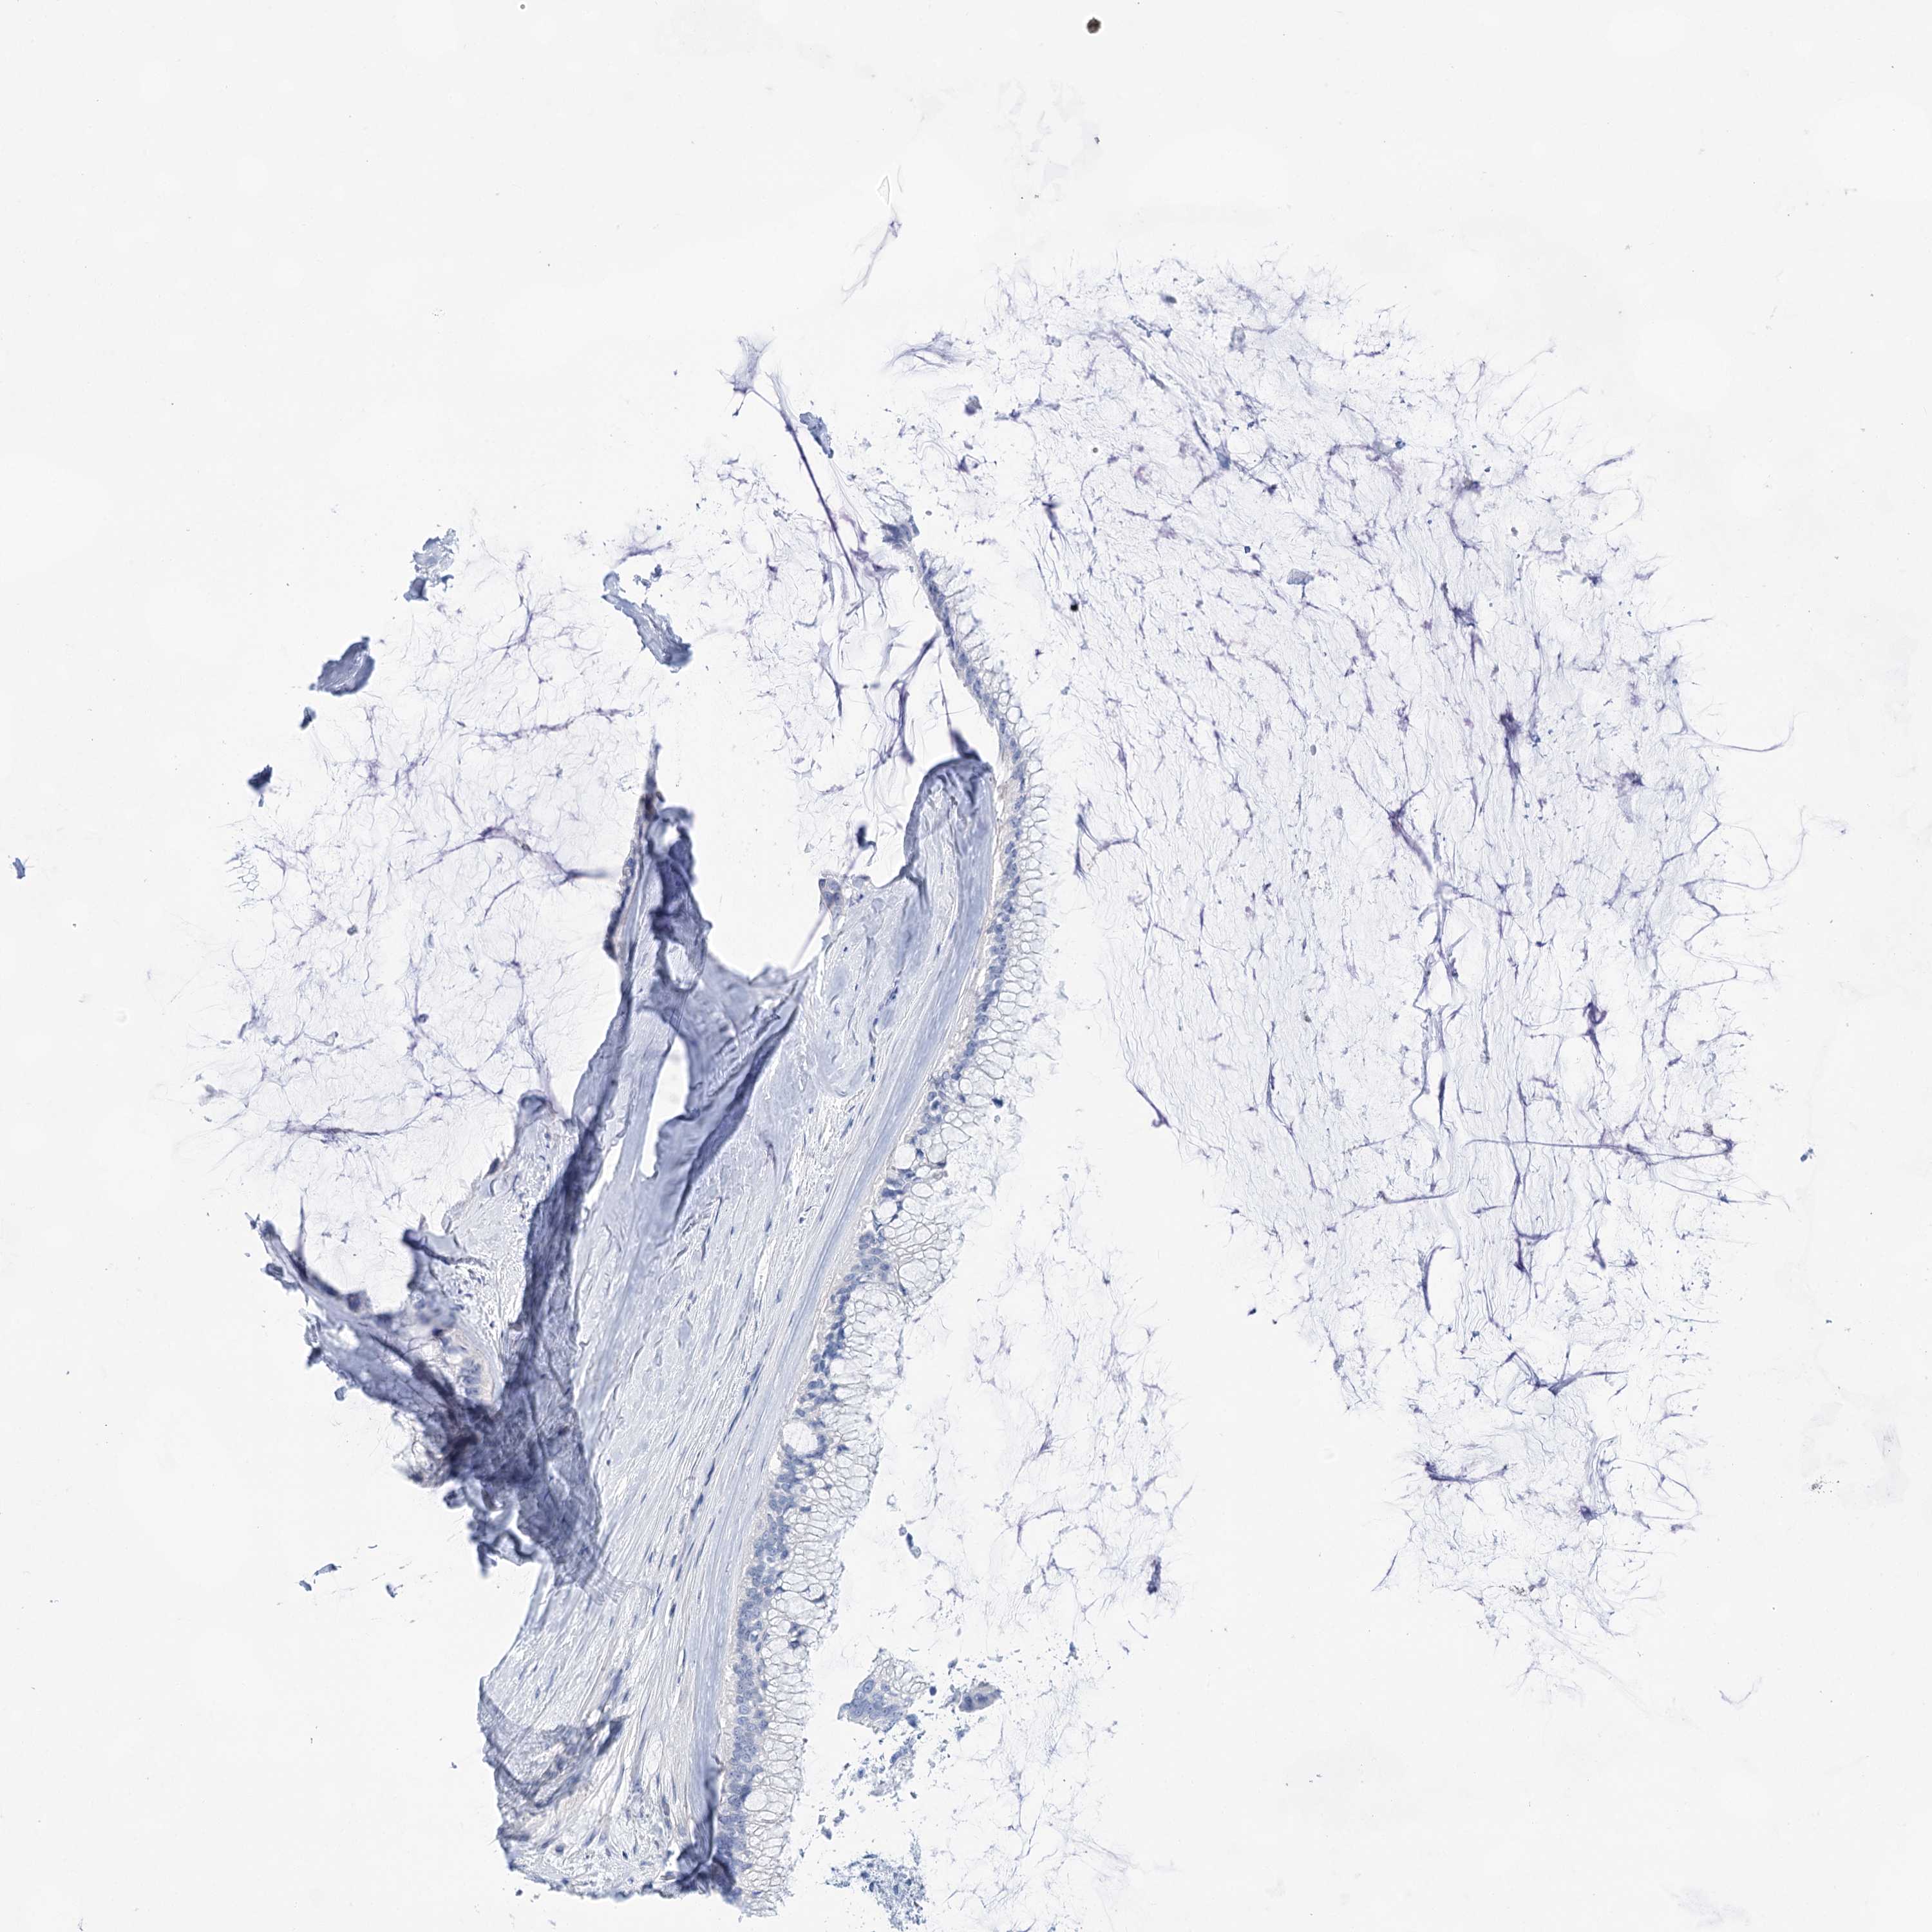

OVARIAN CANCER - Protein expressioni

A mouse-over function shows sample information and annotation data. Click on an image to view it in a full screen mode. Samples can be filtered based on level of antibody staining by selecting one or several of the following categories: high, medium, low and not detected. The assay and annotation is described here.

Note that samples used for immunohistochemistry by the Human Protein Atlas do not correspond to samples in the TCGA dataset.

Antibody stainingi

Antibody staining in the annotated cell types in the current human tissue is reported as not detected, low, medium, or high, based on conventional immunohistochemistry profiling in selected tissues. This score is based on the combination of the staining intensity and fraction of stained cells.

Each image is clickable and will lead to virtual microscopy that enables deeper exploration of all samples and also displays staining intensity scores, fraction scores and subcellular localization as well as patient and tissue information for each sample.

Antibody HPA029855

Antibody HPA029856

Antibody CAB026343

Cystadenocarcinoma, serous, NOS

Carcinoma, endometroid

Cystadenocarcinoma, mucinous, NOS

Carcinoma, NOS